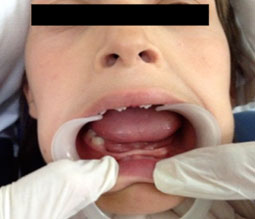

Examen intrabuccal : au maxillaire, on observe un palais en U assez profond, une insertion basse du frein labial et un diastème entre les deux centrales. A la mandibule, on observe une crête très résorbée en lame de couteau semblable à celle du nourrisson (Fig.1) ; une légère inflammation gingivale, une salive abondante et des amygdales sans particularités. La position sagittale et verticale des maxillaires est sans particularités.